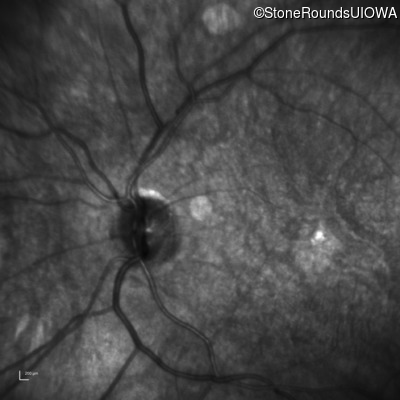

Infrared Fundus Photograph - Left - 20/100

Exemplar